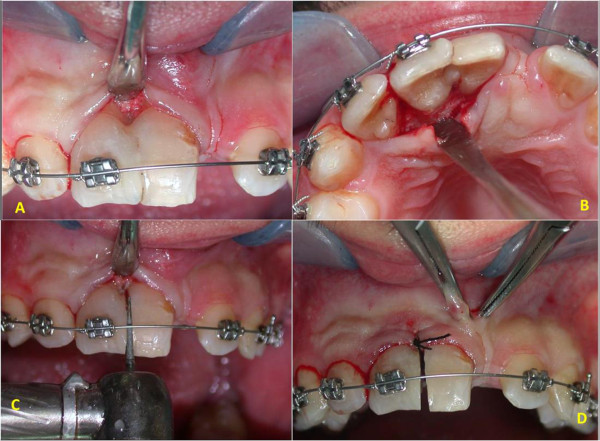

Complete healing of the lesion was obtained six months postoperatively (Figure 5) and orthodontic treatment was initiated after an evaluation of his molar class, overbite, overjet and so on. After one week, orthodontic appliances were put in place (Figure 6). At the same appointment, buccal and palatal flap were raised (Figure 7A,B) and the fused teeth crowns were separated along the buccal groove with a diamond bur (Figure 7C). Because of the presence of an anomalous labial frenulum, a frenulectomy was indicated (Figure 7D).

Figure 7.

Initial orthodontic treatment. (A,B) Exposition of separation groove. (C) Separation of teeth. (D) Frenulectomy.